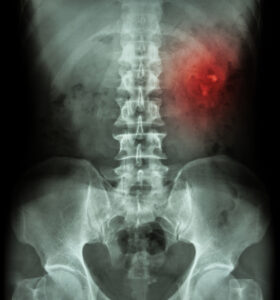

KUB radiography is a non-invasive diagnostic tool that uses x-ray imaging to view the kidneys, ureters, and bladder – the organs in which it receives its name. KUB radiography is typically used to evaluate the condition of these organs, and potential urinary health conditions.

This type of abdominal x-ray is used by urologists when a patient is experiencing unknown pain in their back, flank or abdomen. This diagnostic tool can help identify tumors, urinary blockages and stones in the kidneys, ureters, and bladder.